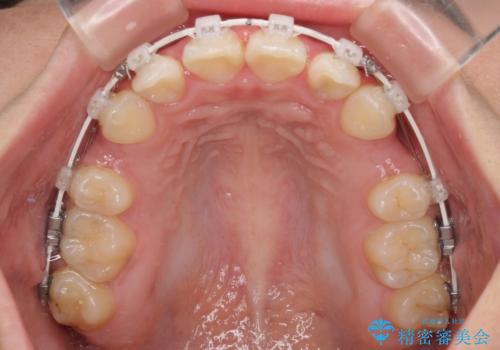

- 矯正装置

- 審美装置

- 2年9ヶ月

- 30回以上

- 下唇の上に乗っかってしまうくらい前歯が飛び出していることを気にして来院された患者様です。

唇を閉じようとするとオトガイ部に力が入ってしまい、うまく閉じることができない状態であったため、上下左右の第一小臼歯4本を抜歯して、ワイヤー装置にて矯正治療を行うこととしました。